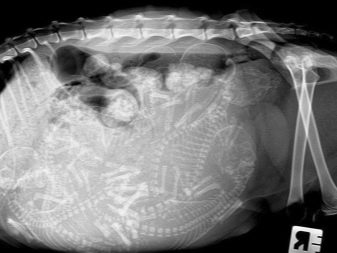

If all the previous points have been successfully completed, and the new couple is ripe for the creation of a feline family, then the process of pregnancy of the cat begins. The process is slow, requiring patience and special care not only for the female, but also for her future offspring. The period of gestation of exotic animals is up to 65 days plus or minus 1-2 days. It is noted that kittens that were born in the period of 50-58 days, usually die immediately.